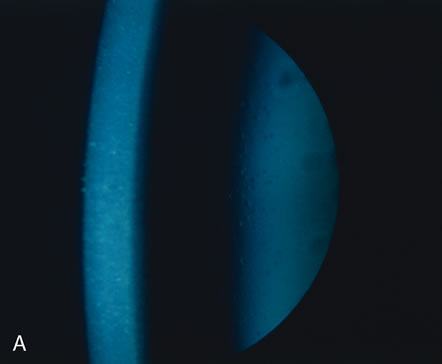

Megalocornea exists when the largest corneal diameter is greater than 13 mm (Fig. 1).19,25 Megalocornea is a primary overgrowth rather than a secondary distention of the cornea.

Fig. 1. Megalocornea. A. The corneal diameter measures 15 mm. The remainder of the eye is normal. B. Megaloglobus consists of an enlarged cornea and globe. C. Megalocornea in the brother of the patient shown in A (a third brother also had megalocornea). The corneal diameter measures 16 mm. D. The crystalline lens is dislocated, and chronic open angle glaucoma is present. (Courtesy of SEI Photoarchives.)